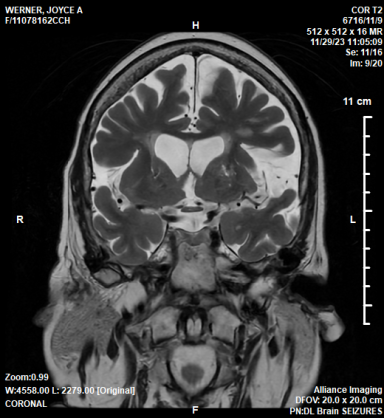

In this series, medical scans—MRI images, X-rays, and other diagnostic views—are transformed into intimate portraits that merge the clinical with the deeply personal. Each work intertwines medical imagery with biographical details, creating a layered visual narrative that honors both the physical realities of illness and the inner lives of those who endure them.

The exhibition features representations of conditions such as multiple sclerosis, lung cancer, hip and knee replacements, a broken wrist, miscarriage, and heartache—each one a story of endurance, adaptation, and faith. The artist wishes to express her gratitude to the patients and their families who entrusted her with creating artworks as unique and special as they are while acknowledging that recovery is never an individual journey; it extends to loved ones who must also heal, grieve, and rediscover vitality in the face of loss or uncertainty.

Mixed media pieces of art derived from the combination of medical scans, surveys from family and friends and genuine creativity from the creator, these artworks are one of a kind.